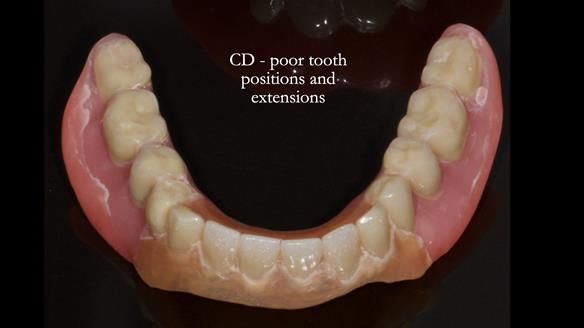

Because her denture space anatomy was limited, I took two working impressions at the same visit. She had very little space in the lower jaw because of the spread of the tongue and the fact she had never worn a lower denture. This made it difficult to judge exactly where the borders needed to be and how much functional space we truly had.

The first impression was my usual Dr Abe shaped impression, which forms the base of my complete denture protocol.

I then made a second working impression using Dr John Besford’s neutral zone approach, known as the French Impression Technique. John learnt this from a dentist in Marseille called Hubert Aiche. I used this technique to record the functional position of the denture borders and tooth space in case the conventional method did not give a stable enough shape.

Both records were processed and compared.

In Sheila’s case, the Dr Abe shaped impression gave a more stable and comfortable result. Sheila preferred the shape produced by the Abe method, so that is the one we used for the registration rims, the trial denture and the final dentures. But making both impressions was worthwhile. It meant we had every option covered and could choose what worked best for her mouth.